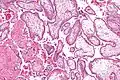

Micrograph showing chorionic villi. Intermediate magnification. H&E stain.

The bulk of the villi consist of connective tissues that contain blood vessels. Most of the cells in the connective tissue core of the villi are fibroblasts. Macrophages known as Hofbauer cells are also present.

They are an essential element in pregnancy from a histomorphologic perspective, and are, by definition, a product of conception. Branches of the umbilical arteries carry embryonic blood to the villi. After circulating through the capillaries of the villi, blood returns to the embryo through the umbilical vein. Thus, villi are part of the border between maternal and fetal blood during pregnancy.